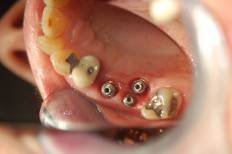

Replace Upper One Molar and One Bicuspids (Three Implants Two Teeth)

Mirror reflection

-Before

Dental Implant

-Implant